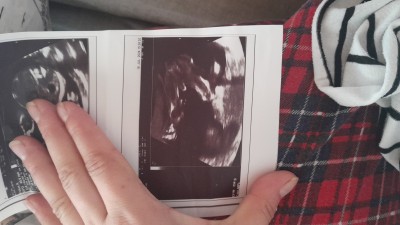

16 da gittim belli değildi 19da pipisi var gibi dedi ama.cevrem kordonla karıştıran oluyor dedi arkadaşım bu ultrason kağıdına elleri diyor ama bacak arası gibi ultrason kağıdından anlayan var mı  cinsiyet tahmini değildir sadece bu kağıdı yorumlayan var mı benimki gibi ola

ortadaki pipi. bebege alttan bakmis iki bacak ve ortadaki pipi

İki bacak ve ortadaki pipi benim oglanında böyle ultrason görüntüsü var :D

Bebeğin nin cinsiyeti erkek büyük ihtimal

Erkek olduğu bayağı belli

Bacak arası pipisi var